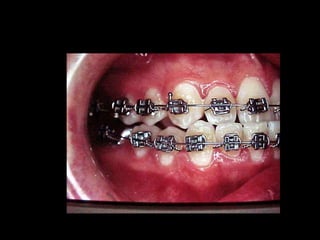

Eliminación de rotaciones.

Corrección de las discrepancias de longitud de arco.

Posición de los incisivos y molares por medio del

torque adecuado.

Llevar cualquier otra alineación en el arco.

Evita el potencial de recidiva

Aumenta la velocidad y eficacia del tratamiento